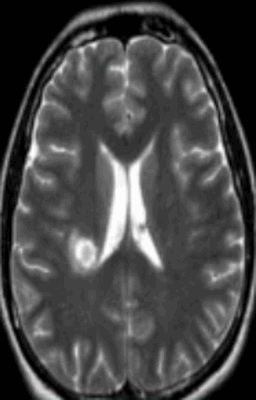

![Очаг демиелинизации на МРТ]()

Очаг демиелинизации на МРТ